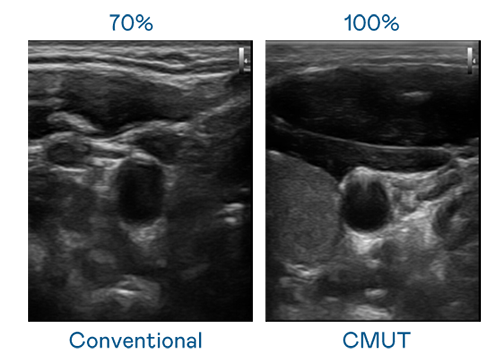

CMUT 技術是一種用電容式微機電元件來產生超音波訊號的技術。與傳統 PZT 壓電式技術相比,CMUT 頻寬增加 30%,更寬頻的超音波訊號讓影像解析度大幅提升,是實現高影像品質醫療超音波掃描、促進精準醫療發展的關鍵技術。

超音波影像的解析度高低,首先取決於探頭能發出的訊號頻寬。公海jcjc5500 CMUT 可提供高清晰的超音波訊號,提供高頻寬、高靈敏度、影像紋理細節更高的超音波影像,協助醫護人員縮短影像判讀時間及利用精準的醫療影像進行診斷。